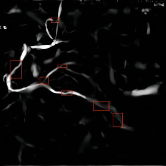

Refer to caption

(a) (a1)

(b) (a2)

(c) (a3)

(d) (b1)

(e) (b2)

(f) (b3)

(g) (c1)

(h) (c2)

(i) (c3)

(j) (d1)

(k) (d2)

(l) (d3)

(m) (e1)

(n) (e2)

(o) (e3)

Figure 6: Overall experimental results of our proposed solution. (a) Original images. (b) Vessel contour extraction after image preprocessing. (c) Vessel segmenting. (d) Automatic stenosis detection. (e) Interactive stenosis detection

Preliminary results

To make a preliminary test on the effectiveness of our proposed solution, we selected three images with large differences in vessel structures for independent experiments and the results are shown in Fig. 6. As can be seen from the figures, even though the vessel structures are different, the whole algorithm in this paper still has a good experimental effect on each image. Next, we will give more detailed and quantitative results of our methods.